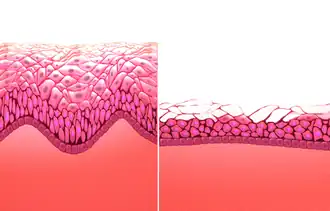

HRT with estrogen and progesterone also improves cholesterol levels. With menopause, HDL decreases, while LDL, triglycerides and lipoprotein a increase, patterns that reverse with estrogen. Beyond this, HRT improves heart contraction, coronary blood flow, sugar metabolism, and decreases platelet aggregation and plaque formation. HRT may promote reverse cholesterol transport through induction of cholesterol ABC transporters.[43] Atherosclerosis imaging trials show that HRT decreases the formation of new vascular lesions, but does not reverse the progression of existing lesions.[44] HRT also results in a large reduction in the pro-thrombotic lipoprotein a.[45]